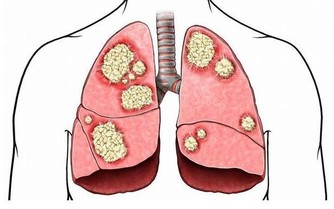

4、多發性骨髓瘤

多發性骨髓瘤這種疾病多發於老年人,並且年齡越大發病率越高,是成正比的,這種疾病最初的表現症狀也是腰痛,但是除了腰痛之外,這個疾病還會侵犯身體其他的骨頭,也就會導致身體其他部位的疼痛,多發性骨髓瘤會侵犯人的運動系統,最嚴重的後果是導致骨折,老年人的骨折往往都是致命的,因為老年人骨折後的臥床會帶來很多的並發症。

多發性骨髓瘤這種疾病多侵犯人的骨頭、骨髓,所以常常腰痛伴有周身疼痛,並且多發性骨髓瘤這種疾病也是一種惡性腫瘤,如果家裡的老人長時間的腰痛就要帶著去醫院檢查一下,排查一下多發性骨髓瘤。